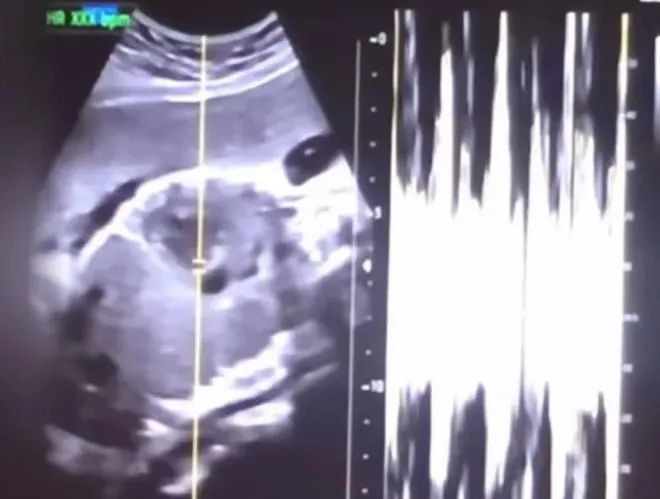

最近,韩国爆出了一桩让人脊背发凉的案子…一名韩国女子怀孕36周时堕胎,某医院院长和医生竟然对36周的胎儿实施剖腹产,然后直接塞进冰箱致死。 警方细查下来,发现这起案子不仅涉及谋杀、伪造医疗记录、非法堕胎,甚至还牵扯到巨额黑色产业链… ![]() 去年6月25日,20岁、怀孕36周的权女士试图寻找一家医院为她做堕胎手术,由于她怀孕月份太大,接连被两家医院拒绝,几经辗转终于找到了一位愿意接收她的尹医生。 尹医生是一家医院的院长,80岁高龄,专门接收怀孕24周以上被其他医院拒绝堕胎的孕妇。 于是权女士就在尹医生的医院里进行了手术。 说是堕胎手术,其实是剖腹产手术…胎儿从她腹中取出后,被医生用一块布包住,塞进了医院的冰箱冷冻,导致胎儿死亡。 事后,尹医生在权女士的病历上写上“出血、腹痛”等假信息,把堕胎手术写成“自然死产”。他甚至开了假诊断书,写着“卵巢囊肿切除”,试图掩盖真相。 权女士再把假的死产证明交给火化机构,将婴儿火化。 ![]() (权女士怀孕) 这起堕胎案件原本没有漏洞,但是怎么被发现的呢…是权女士自己公开的。 权女士把自己36周堕胎的经历拍成视频,取名《手术费总计900万韩元,120小时的地狱生活》,上传到YouTube。 她自称不知道自己怀孕,发现时胎儿已经满36周,因为不想要小孩,在多方艰难咨询下才顺利堕胎,打算把堕胎过程拍成纪录片分享。 视频里面有胎儿的超音波影像,当时胎儿几乎已经发育完全。甚至还有她堕胎手术后的恢复过程,在互联网上引发了巨大争议… ![]() (权女士视频截图) 根据韩国现行《母婴保健法》规定,除非孕妇出现健康或生命危险等特殊情况,否则禁止怀孕24周后堕胎。 所以视频发出之后,有人质疑视频的真实性,也有人愤怒指责这是谋杀。 权女士赶紧删掉了视频,还改了账号名字,关闭了评论区,发了吃播视频遮掩… ![]() (权女士视频) 但这视频还是闹到了韩国保健福祉部,警方也介入了调查,查了才知道,事情远比想象中更黑暗…权女士的事只是冰山一角。 经过调查发现,尹医生的医院这两年来专门接收“高危堕胎”孕妇,尤其是那些怀孕24周以上,其他医院不敢接的案例。 他们和一家中介合作,通过中介介绍,两年时间里接待了527名堕胎客户,其中59名孕妇是被其他医院拒绝的“大月份堕胎”案例,总共赚了14.6亿韩元(约780万人民币),其中3.12亿韩元,作为分成付给了中介。 ![]() (视频中截取的超声波图像和心率图表) 原本尹医生的医院已经陷入了经营困境,但通过堕胎手术赚钱之后,医院扭亏为盈,于是他跟政府申请不再接普通病人,甚至关闭普通病房,只做堕胎手术,变成“堕胎专科”。 更讽刺的是,尹医生年事已高,自己没法做手术,就雇了通过熟人认识的60岁的大学医院外科医生沈医生来操刀,每台手术给几十万韩元(约几千人民币)的报酬。 而尹家医院之所以敢这么肆无忌惮做“大月份”堕胎手术,是因为韩国的法律留了个空子… ![]() (权女士视频截图) 其实韩国在2019年之前,刑法中有明确处罚堕胎行为的条款,可2019年宪法法院判决这些处罚条款"违宪",要求2020年12月31日前修改法律。 国会争论不下至今没完成法律修改,导致法律"真空期"出现。 总之,目前没有可以处罚堕胎行为的有效法律依据,一些黑心医生钻空子,肆意做大月份堕胎手术。 尹医生等人就是利用这个漏洞,把堕胎当成生意做,甚至不惜谋杀婴儿来掩盖罪行。 案件曝光后,韩国网友集体跑来抨击… “我为那些丧生的孩子的灵魂祈祷,这是谁的错,有用吗…” ![]() (评论区截图) “堕胎是天理难容的杀人行为!根本无需多言。” ![]() (评论区截图) 检方的态度是必须严惩,这个月,首尔中央地方检察厅刑事第三部已经以谋杀、违反《医疗法》以及开具和使用虚假医疗证明的罪名逮捕并起诉了尹医生。 实施剖腹产手术的沈医生,20岁的权女士也因为涉嫌谋杀共犯而被逮捕起诉。中介也被一锅端… 根据韩国过往的记录,曾经有医生因替怀孕34周的孕妇堕胎,而遭判刑3年…尹医生和沈医生这回大概率逃不过法律的制裁。 这起案子最可怕的地方在于有人把生命当成了生意,甚至用冰箱来结束一个即将出生的婴儿的生命。 说到底,只有法律完善,才可能让类似的黑色产业链彻底消失。 |